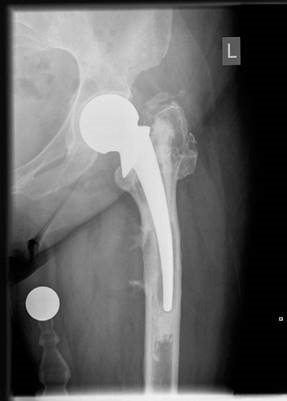

Structured Oral Hip Examination Question 3 EXAMINER : This is an anteroposterior (AP) radiograph of a 78-year…

Structured Oral Hip Examination Question 7 EXAMINER : This is a radiograph of a 68-year-old woman who has bee…

Structured Oral Hip Examination Question 6 EXAMINER : This is an anteroposterior (AP) radiograph of a 72year-…